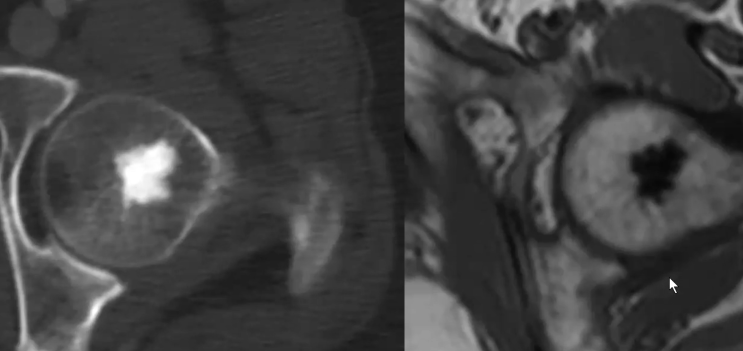

Ilot Ostéocondensant

- Densité ivoire (>885 = très spécifique)

- Marges en “épines”

Enostose Géante

- Sont >2-3 cm

- Pelvis ++

- Peut capter un peu au PET (pas plus que l’aile iliaque adjacente, tandis qu’un ostéosarcome de bas grande capterait ++)